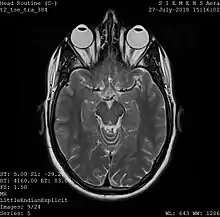

Magnetic resonance imaging

A magnetic resonance imaging instrument (MRI scanner), or "nuclear magnetic resonance (NMR) imaging" scanner as it was originally known, uses powerful magnets to polarize and excite hydrogen nuclei (i.e., single protons) of water molecules in human tissue, producing a detectable signal which is spatially encoded, resulting in images of the body.[5] The MRI machine emits a radio frequency (RF) pulse at the resonant frequency of the hydrogen atoms on water molecules. Radio frequency antennas ("RF coils") send the pulse to the area of the body to be examined. The RF pulse is absorbed by protons, causing their direction with respect to the primary magnetic field to change. When the RF pulse is turned off, the protons "relax" back to alignment with the primary magnet and emit radio-waves in the process. This radio-frequency emission from the hydrogen-atoms on water is what is detected and reconstructed into an image. The resonant frequency of a spinning magnetic dipole (of which protons are one example) is called the Larmor frequency and is determined by the strength of the main magnetic field and the chemical environment of the nuclei of interest. MRI uses three electromagnetic fields: a very strong (typically 1.5 to 3 teslas) static magnetic field to polarize the hydrogen nuclei, called the primary field; gradient fields that can be modified to vary in space and time (on the order of 1 kHz) for spatial encoding, often simply called gradients; and a spatially homogeneous radio-frequency (RF) field for manipulation of the hydrogen nuclei to produce measurable signals, collected through an RF antenna.

Like CT, MRI traditionally creates a two-dimensional image of a thin "slice" of the body and is therefore considered a tomographic imaging technique. Modern MRI instruments are capable of producing images in the form of 3D blocks, which may be considered a generalization of the single-slice, tomographic, concept. Unlike CT, MRI does not involve the use of ionizing radiation and is therefore not associated with the same health hazards. For example, because MRI has only been in use since the early 1980s, there are no known long-term effects of exposure to strong static fields (this is the subject of some debate; see 'Safety' in MRI) and therefore there is no limit to the number of scans to which an individual can be subjected, in contrast with X-ray and CT. However, there are well-identified health risks associated with tissue heating from exposure to the RF field and the presence of implanted devices in the body, such as pacemakers. These risks are strictly controlled as part of the design of the instrument and the scanning protocols used.

Because CT and MRI are sensitive to different tissue properties, the appearances of the images obtained with the two techniques differ markedly. In CT, X-rays must be blocked by some form of dense tissue to create an image, so the image quality when looking at soft tissues will be poor. In MRI, while any nucleus with a net nuclear spin can be used, the proton of the hydrogen atom remains the most widely used, especially in the clinical setting, because it is so ubiquitous and returns a large signal. This nucleus, present in water molecules, allows the excellent soft-tissue contrast achievable with MRI[6].

A number of different pulse sequences can be used for specific MRI diagnostic imaging (multiparametric MRI or mpMRI). It is possible to differentiate tissue characteristics by combining two or more of the following imaging sequences, depending on the information being sought: T1-weighted (T1-MRI), T2-weighted (T2-MRI), diffusion weighted imaging (DWI-MRI), dynamic contrast enhancement (DCE-MRI), and spectroscopy (MRI-S). For example, imaging of prostate tumors is better accomplished using T2-MRI and DWI-MRI than T2-weighted imaging alone.[7] The number of applications of mpMRI for detecting disease in various organs continues to expand, including liver studies, breast tumors, pancreatic tumors, and assessing the effects of vascular disruption agents on cancer tumors.[8][9][10]